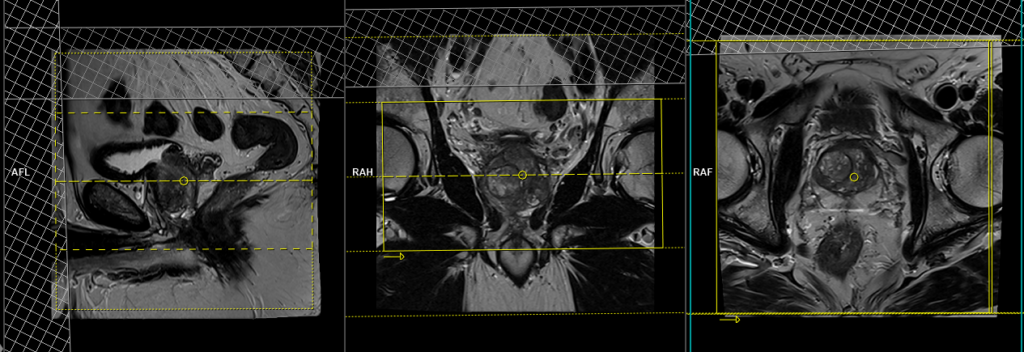

T2 tse coronal 3mm SFOV

Plan the coronal slices on the sagittal plane and angle the positioning block vertically across the prostate, as shown in the picture. Check the positioning block in the other two planes, ensuring an appropriate angle is given in the axial plane (parallel to the right and left hip joints or ischial tuberosity). The slices must be sufficient to cover the entire prostate and seminal vesicles. Additionally, to minimize artifacts stemming from arterial pulsation and breathing, consider incorporating saturation bands on the top and front of the coronal block.

Parameters

TR 3000-4000 | TE 100-120 | SLICE 3 MM | FLIP 130-150 | PHASE R>L | MATRIX 320X256 | FOV 180-230 | GAP 10% | NEX(AVRAGE) 5 |